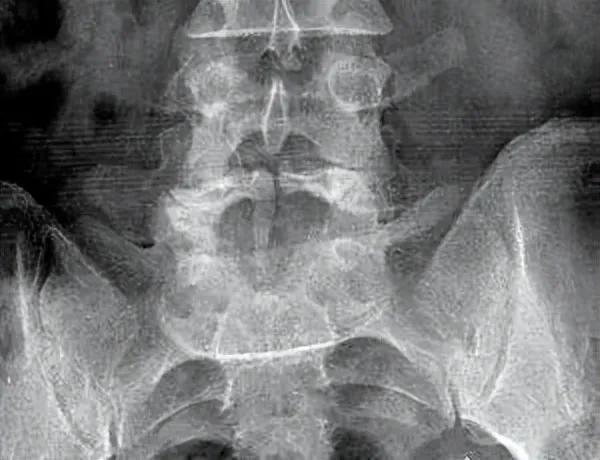

在诊断腰突症的过程中,医生通常会根据患者的症状和体征,选择适当的影像学检查方法。目前常用的检查方法包括X线、CT和MRI三种。X线检查主要用于排除其他骨性病变,如骨折、肿瘤等。CT检查可以清晰显示椎间盘突出的部位、大小和形态,以及神经根受压的情况。MRI则能更准确地显示椎间盘突出的位置和程度,以及对脊髓和神经的压迫情况。

那么,为什么在已经做过MRI的情况下,医生还可能要求做CT和X线检查呢?这主要是因为每种检查方法都有其独特的优点和局限性。MRI虽然能清晰显示软组织结构,但在显示骨性结构方面不如CT。CT虽然能清晰显示骨性结构,但在显示软组织结构方面不如MRI。X线检查虽然分辨率较低,但能快速、直观地显示脊柱的整体结构。因此,结合使用这三种检查方法,可以更全面、准确地评估患者的病情。